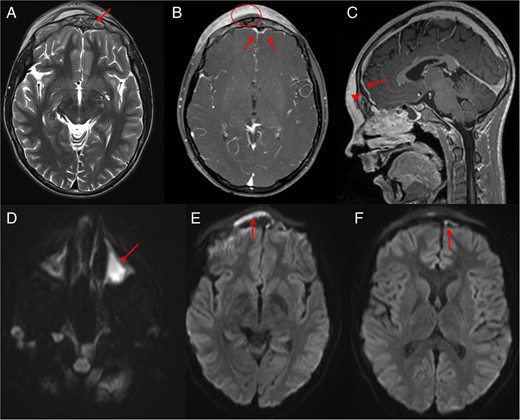

Two days following this procedure, the patient had persistent tenderness over the forehead. At this point, we decided to proceed to magnetic resonance imaging (MRI) (Fig. 2) to further evaluate the frontal bone and extra-axial spaces. These images confirmed abnormal signal within the frontal bone in keeping with osteomyelitis. Post-contrast-enhanced images demonstrated scalp and intra-dural enhancement. Diffusion-weighted images confirmed an evolving epidural abscess that was encroaching and slightly compressing the superior sagittal sinus, although the sinus remained patent with no evidence of thrombosis.

Post-drainage of right maxillary sinus and right orbital subperiosteal abscess MRI was performed. MRI shows abnormal signals (arrow) from the anterior frontal bone suggesting osteomyelitis (A). Post-contrast MRI demonstrates the scalp Pott's puffy tumour (circle) with surrounding scalp enhancement. MRI (B) also shows reactive dural enhancement and an epidural abscess that is better seen (arrowhead) on sagittal sequence (C) compressing the superior sagittal sinus (arrow) which is not thrombosed. Diffusion images (D–F) confirm pus in left maxillary sinus (D), scalp subperiosteal abscess (E) and intracranial extra-axial (F) epidural abscess (arrows).